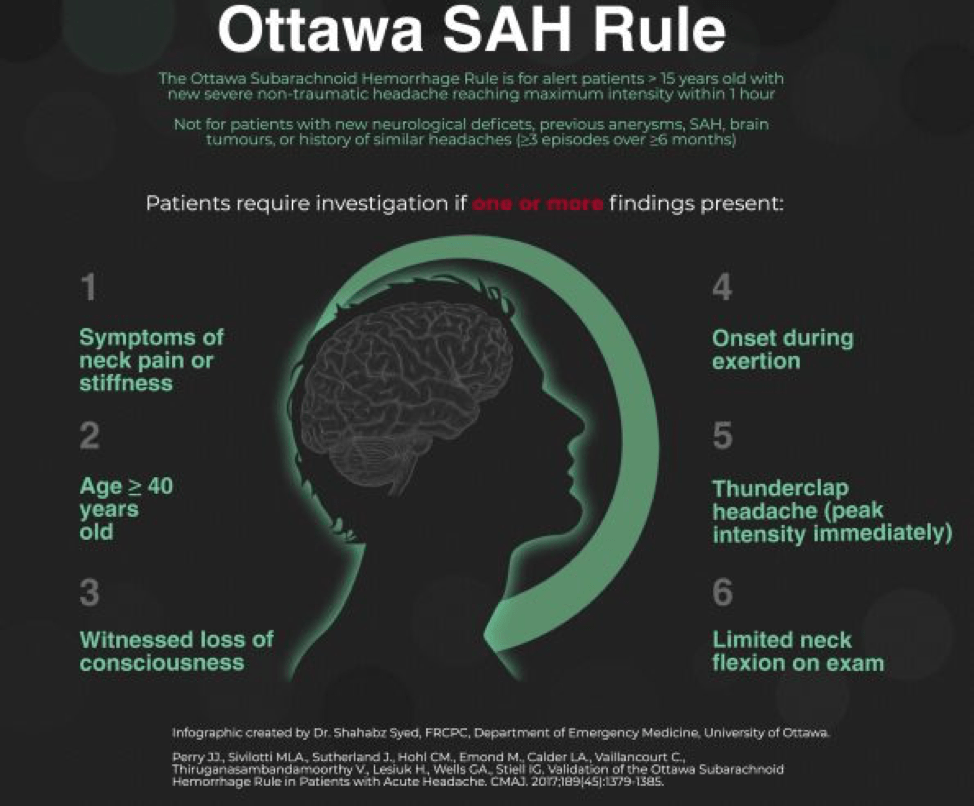

In a patient that doesn’t have such obvious symptoms, the Ottawa SAH Rule can help guide decision-making. You’ll notice that many of the components of the rule are also on the list of red-flag symptoms for headache, which you can read about in this great article. However, the rule should be used with caution as it has not yet been fully validated across a broad enough range of populations yet to be considered prime-time. You can read more about how to use the Ottawa SAH Rule here or here.